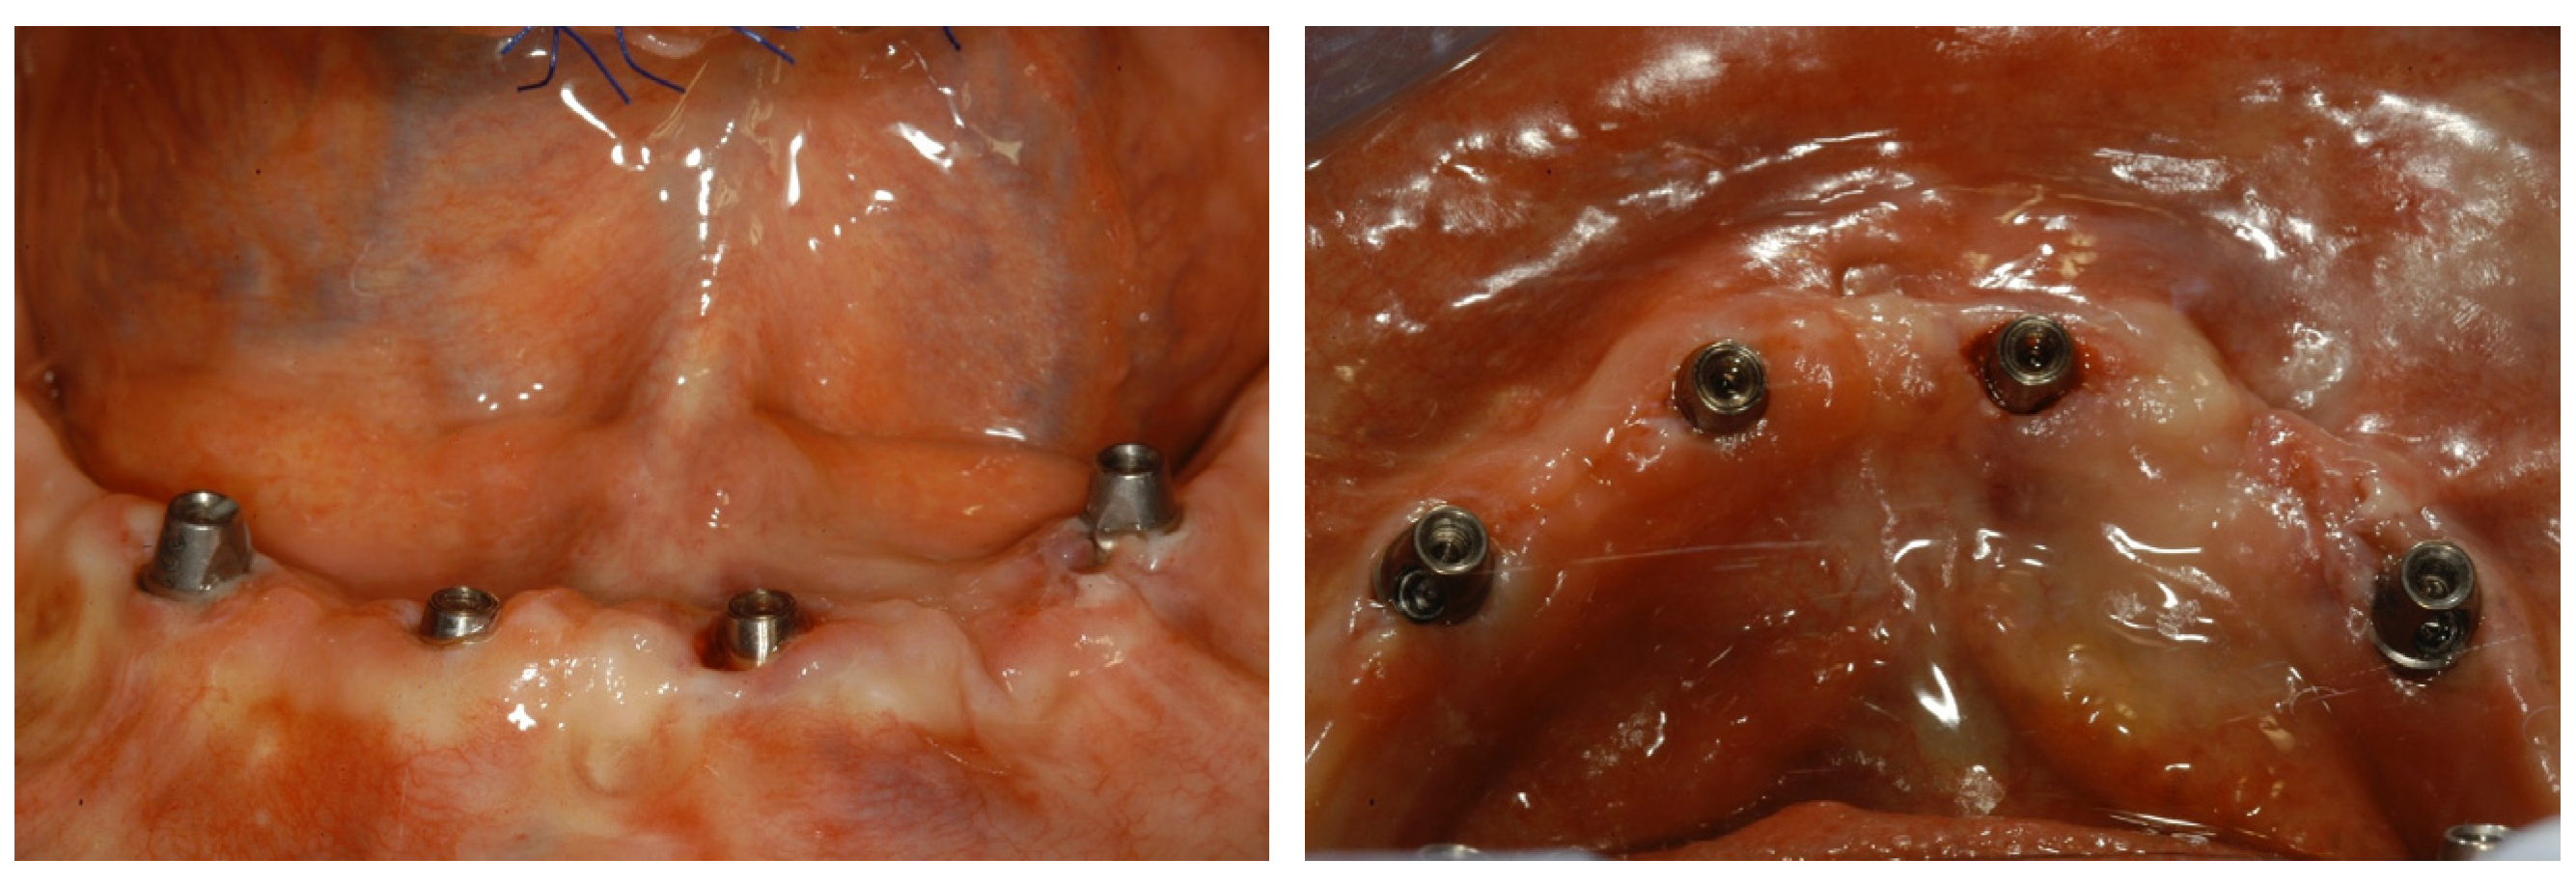

Computer-guided workflow: The same procedures as those described in a previous article were carried out [6]. In brief, a preliminary prosthetic wax-up, corresponding to the exact replica of the final prosthesis accepted by the patient, integrated with aesthetic and functional principles was realized. Then, a radiological stent was fabricated on the basis of the preliminary prosthetic wax-up as a duplication of the final prosthesis. The said stent was equipped with an extraoral radiopaque marker for 3D position tracking, necessary during the subsequent superimposition of the scans. Each subject underwent a CBCT scan of the edentulous jaw while wearing the radiopaque stent in order to integrate the anatomical data with the functional and aesthetic parameters. Subsequently, an optical scan of the prosthesis itself was performed, as required by the digital workflow. The aforesaid scans were imported and matched within the planning software, and the ideal virtual 3D implant position was decided according to the prosthetic design and the jaw’s anatomy by the surgeon, a dental expert in dental prosthesis, and an experienced dental technician in charge of the fabrication of temporary and definitive prostheses. The overlapping was possible thanks to the processing of the data in stereolithographic interface format (STL) acquired from the optical scan superimposed on the data obtained from the CT device using the DICOM format, further using the geometric marker present in both scans. This allowed the simultaneous display of the axial, 3D, panoramic, and transverse images integrated with the prosthetic profile on the computer monitor. Technically, the All-on-4 treatment concept surgical protocol was generally followed [9]. In brief, the two most anterior straight implants followed the bone anatomy in terms of direction. The two posterior implants were inserted just anterior to the foramina or tangent to the maxillary sinus and were tilted distally by approximately 30°, or up to 45° when needed, relative to the occlusal plane. The aim was to reduce, as much as possible, the cantilever’s length and increase the interimplant’s distance, as the posterior implants typically emerged at the second premolar position. Care was taken to avoid conflict between the apices of the anterior and the tilted posterior implants. In the case of thin residual bone crests, implants were tilted slightly palatally/lingually in order to follow the jaw’s anatomy, engage both buccal and palatal/lingual cortical plates, and achieve adequate primary stability. Straight or angled definitive abutments of variable heights were chosen from the library so that prosthetic screw access holes were in occlusal or lingual/palatal locations to allow an acceptable thickness of the prosthesis and to facilitate passive fitting. At this point, the virtual project was transferred into a surgical guide by means of rapid prototyping and stereolithography techniques. All surgical procedures were performed by the same surgeon on an outpatient basis under local anesthesia. The surgical stent was fixed in the correct position using a silicone index, with the guided insertion of surgical pins on the buccal side of the alveolar process according to the virtual plan in order to preserve anatomical structures. The guide allowed the use of calibrated drills, without changing the metal cylinders contained in the stents up to the implant’s insertion. Initially, circular mucosal operculectomy was performed with a surgical mucotome to remove the gingival plug from the implant site, followed by serial osteotomies performed using disposable internally cooled drills, until the planned depth was reached. The implants (Screw-line Camlog Guide, Promote Plus, Camlog Biotechnologies, Basel, Switzerland) were then placed in the desired position according to the manufacturer’s instructions. After the removal of the pins and surgical template, definitive abutments were screwed to the implants (Figure 1).

A temporary screw-retained prosthesis that was relined intraoperatively was finally delivered to the patient. An occlusal check and adjustment were performed to attain optimal distribution of mastication forces. The final rehabilitation was delivered after 6 months, and follow-up orthopantomography was performed (Figure 2).

Figure 1. Frontal and occlusal view of peri-implant soft tissues around definitive abutments screwed to the implants.